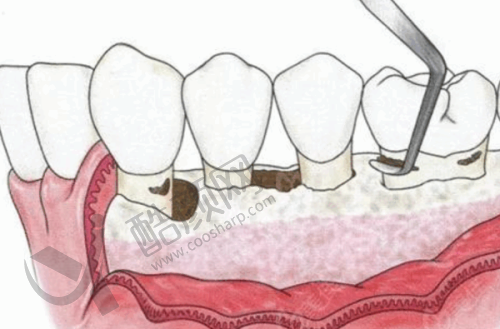

首先,肖步挺医生种牙资质正规,拥有相关认证,是深圳尔睦口腔连锁认证医生,正规可靠。其次,他种牙临床经验多,从事口腔种植临床工作已有超过二十年的经验,积累了丰富的临床和处理各种复杂情况的能力,不仅掌握了种植牙的基础技术,还不断学习和跟进新的种植技术和理念。再者,他在种植牙技术上有着不错的技艺和独特的见解,擅长数字化微创种牙、全口无牙颌种植修复、即刻拔牙即刻种植等多种技术,能根据顾客的口腔情况和需求,制定个性化的手术方案,确保种植牙的稳定性。众多顾客对肖步挺医生的种植牙技术和服务给予了高度评价,称赞他种牙技术在线、态度亲切、耐心细致,能够在手术前后给予患者充分的关怀和指导,确保患者能够顺利修复。此外,他做种植牙服务流程精细,会详细询问患者的病史和口腔情况,进行全方面的口腔检查和评估,然后根据患者的需求和情况制定个性化的手术方案,在手术过程中,严格按照标准操作流程进行,确保手术的成功。末尾,他所在的深圳尔睦口腔医院收费价格透明公正,会根据患者的具体情况和手术难度进行合理的收费,并会提前告知患者相关费用明细,避免产生不必要的误解和纠纷,且术后跟踪服务到位,会定期安排术后跟踪服务,询问患者的情况,解答患者的疑问,并根据患者的实际情况给予相应的指导和建议,让患者感到更加安心和放心。